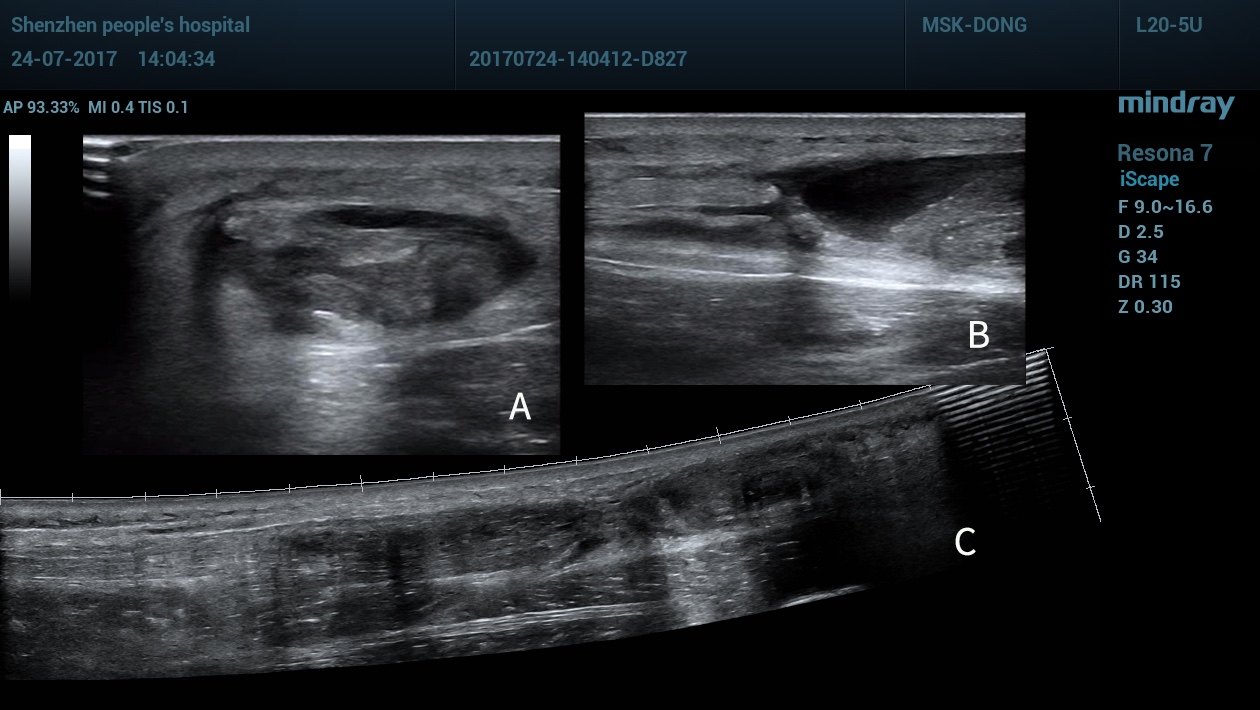

美图欣赏61网球腿(跖肌腱撕裂)_超声_血肿_箭头

图片尺寸1080x759

景长轴成像,b短轴成像,c双侧对比扫查,显示跟腱肿胀,浅方肌腱局部撕裂